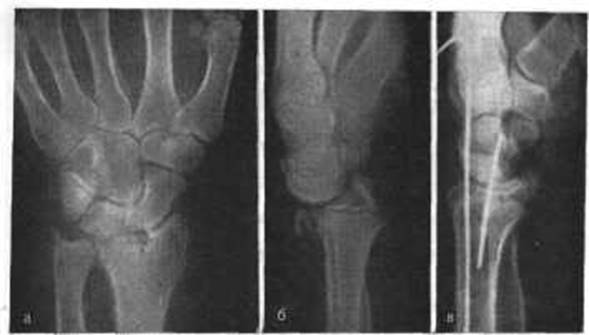

Перелом Полулунной Кости Кисти Руки Фото

Перелом Полулунной Кости Кисти Руки Фото 114 фото